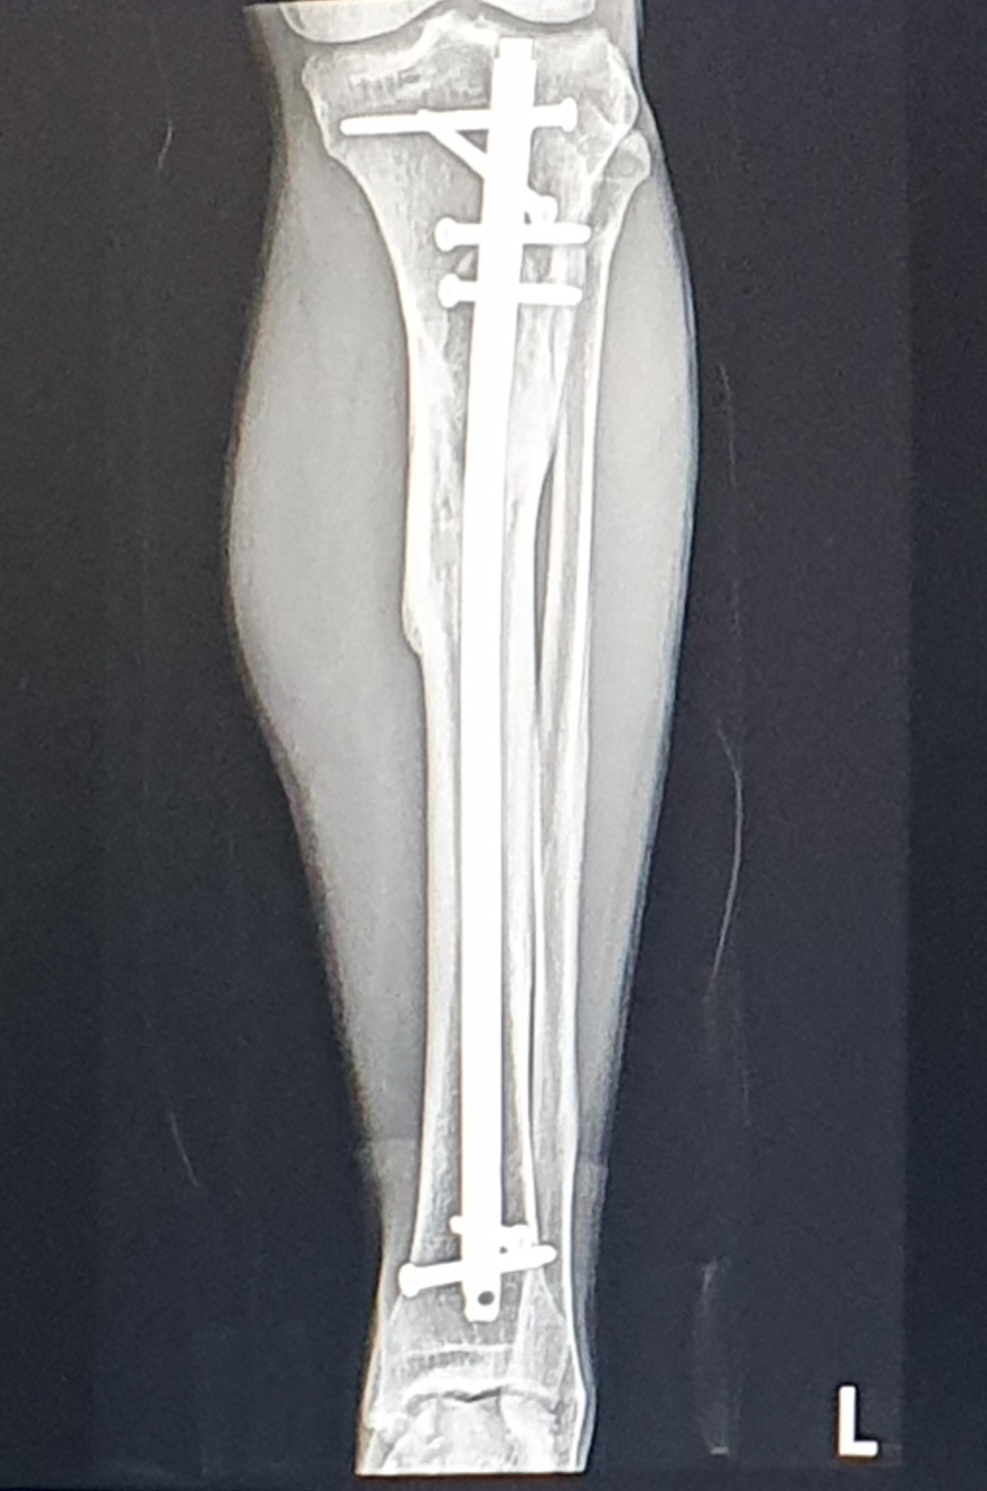

"잘 붙었네요. 철심 제거 수술을 해도 괜찮아요."

화면에 올라온 X-ray 사진을 보니 8개월 전과는 확연히 달랐다.

낙상사고 당시의 비수술 상태에서 찍은 사진과 비교해서도 엄청난 진전이다.

"그럼 절심제거 수술 하겠습니다."

설을 쇤 후 2월 16일 수술 결정, 일사천리로 진행된다.